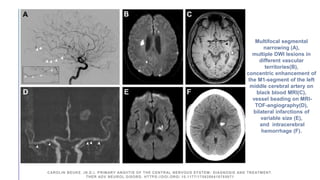

Multifocal segmental

narrowing (A),

multiple DWI lesions in

different vascular

territories(B),

concentric enhancement of

the M1-segment of the left

middle cerebral artery on

black blood MRI(C),

vessel beading on MRI-

TOF-angiography(D),

bilateral infarctions of

variable size (E),

and intracerebral

hemorrhage (F).